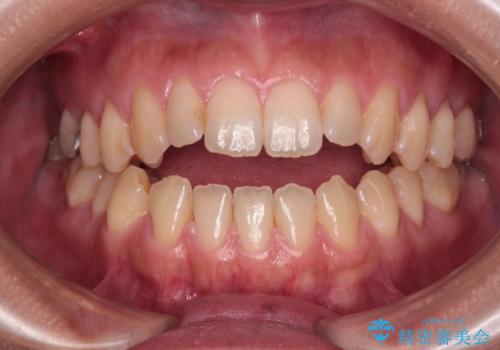

長年気になっていた前歯 矯正治療と補綴治療による審美歯科治療